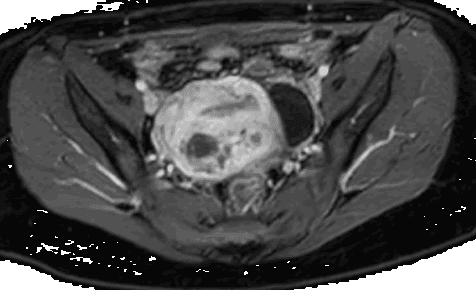

Manejo histeroscópico de la adenomiosis quística submucosa

La adenomiosis es una condición benigna del útero caracterizada por la presencia de glándulas endometriales y estroma que invaden el miometrio con presencia de hiperplasia e hipertrofia de las fibras musculares lisas. Ocurre principalmente en mujeres entre la cuarta y la quinta década de la vida. La adenomiosis a menudo se asocia a factores de riesgo como multiparidad, cirugía uterina previa y presencia de endometriosis; y al igual que este último, también es sensible a los estrógenos. Si bien algunas mujeres diagnosticadas con adenomiosis no presentan síntomas, la enfermedad puede causar: 1. Sangrado menstrual abundante y prolongado 2. Cólicos menstruales severos 3. Presión abdominal e hinchazón La adenomiosis tiene dos formas de presentación que se describen como focales y difusas. La adenomiosis focal puede ocurrir como una lesión nodular bien circunscrita (adenomioma), similar a un fibroma intramural o restringida a una estructura de la pared uterina en forma de adenomiosis localizada. Por el contrario, la forma difusa es aquella en la que puede afectar a todo el útero sin límites demarcados entre el tejido invadido y el miometrio sano circundante. Hasta hace poco, la única forma definitiva de diagnosticar la adenomiosis era realizar una histerectomía y examinar el tejido uterino con un microscopio. Sin embargo, la tecnología de imágenes ha hecho posible que los médicos reconozcan la adenomiosis sin cirugía. Mediante resonancia magnética o ecografía transvaginal, los médicos pueden ver las características de la enfermedad en el útero. Con el uso de técnicas de imagen modernas mejoradas, es posible que un número creciente de casos en adolescentes y mujeres adultas jóvenes con dismenorrea, emerja un nuevo tipo de adenomiosis llamada "quística". En la actualidad, el diagnóstico se basa principalmente en la resonancia magnética, presentándose como una estructura quística con un diámetro interno ≥10 mm y contenido hemorrágico rodeada de tejido miometrial. En una revisión de la adenomiosis quística, Brosens et al (2015) describieron tres tipos (A, B y C) con sus respectivos subtipos, según la ubicación del quiste y la complejidad de la lesión. Si un médico sospecha de adenomiosis, el primer paso es un examen físico. Un examen pélvico puede revelar un útero agrandado y sensible. Una ecografía puede permitirle al médico ver el útero, su revestimiento y su pared muscular. Aunque la ecografía no puede diagnosticar definitivamente la adenomiosis, puede ayudar a descartar otras afecciones con síntomas similares.